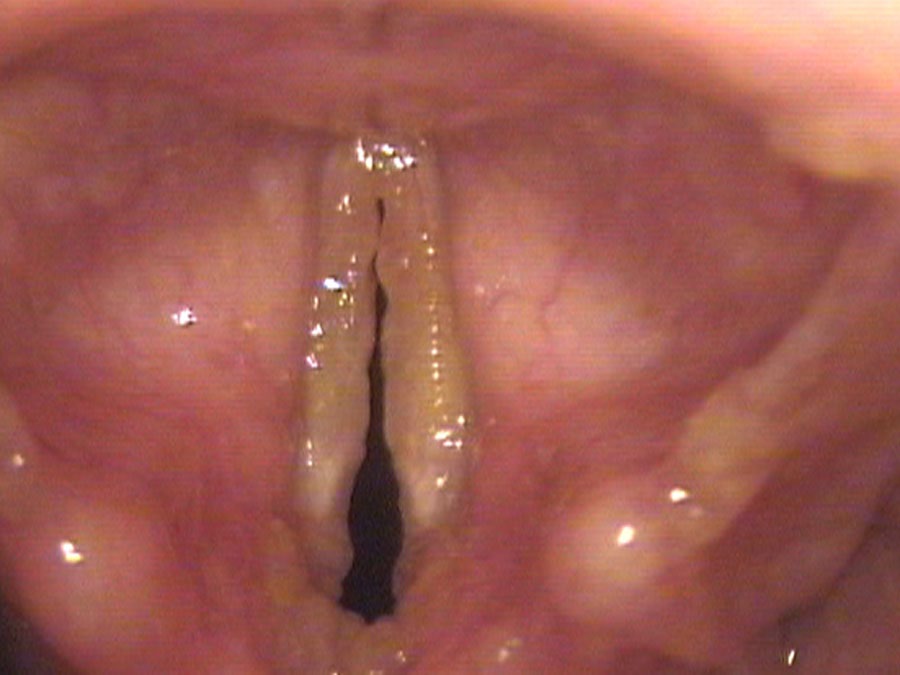

Christina Amarillo is 30 and has been getting progressively more hoarse for the past 10 years. Her mother and three aunts are all hoarse. One of her aunts had surgery and amyloid was removed from her vocal cords. Listening to Christina’s husky voice, she leaks air. On endoscopy there are patches of yellow material underneath the mucosa of the vocal cords. These vocal cords are stiff and do not come completely together because of the yellow deposits.

In this condition, blood vessels seem to break easily and rather than the body reabsorbing all the blood, a yellow material is left as a deposit where the bleeding occurred. Deposits on the edge of the vocal cord create an irregular edge such that air leaks between the cords (huskiness) and the deposits create differences in stiffness and mass between the cords so that they vibrate at different pitches at times (roughness). Eventually more effort is required to start them vibrating.

Blood vessels seem to break easily and rather than the body reabsorbing all the blood, a yellow material is left as a deposit where the bleeding occurred — gradually building up along the vibrating edge of the cord.